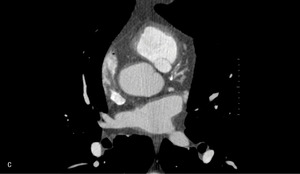

Rycina 2. Badanie tętnic wieńcowych metodą tomografii komputerowej. A. Rekonstrukcja MIP Inwers (maksimum intensity projection) – widoczne wielopoziomowe zmiany w prawej tętnicy wieńcowej. B. Warstwa poprzeczna (axial) – obraz remodelingu dodatniego ściany naczynia w segmencie 3 prawej tętnicy wieńcowej; blaszka niskiej gęstości zwęża światło w 40%, jednak jej faktyczna wielkość ukryta jest dzięki modelowaniu ściany naczynia na zewnątrz.

– Prawa tętnica wieńcowa (PTW): segment 1 – uwapnione wielopoziomowe zmiany ~30% przechodzą w blaszkę niskiej gęstości ~60%; segment 2 – wielopoziomowe blaszki mieszanej gęstości ~30%; segment 3 – blaszki niskiej gęstości ~30-50% z remodelingiem dodatnim ściany naczynia (!). Obwód – zmiany przyścienne (ryc. 2).